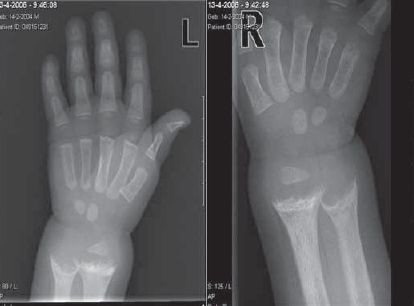

Een allochtone peuter met kromme beentjes

De afgelopen jaren krijgt het belang van vitamine-D-toediening bij bepaalde risicogroepen (zoals niet-westerse allochtonen en ouderen) opnieuw aandacht. Niet-westerse allochtonen lopen vooral risico op vitamine-D-deficiëntie door een gebrek aan zonlicht in combinatie met een vaak donkere…